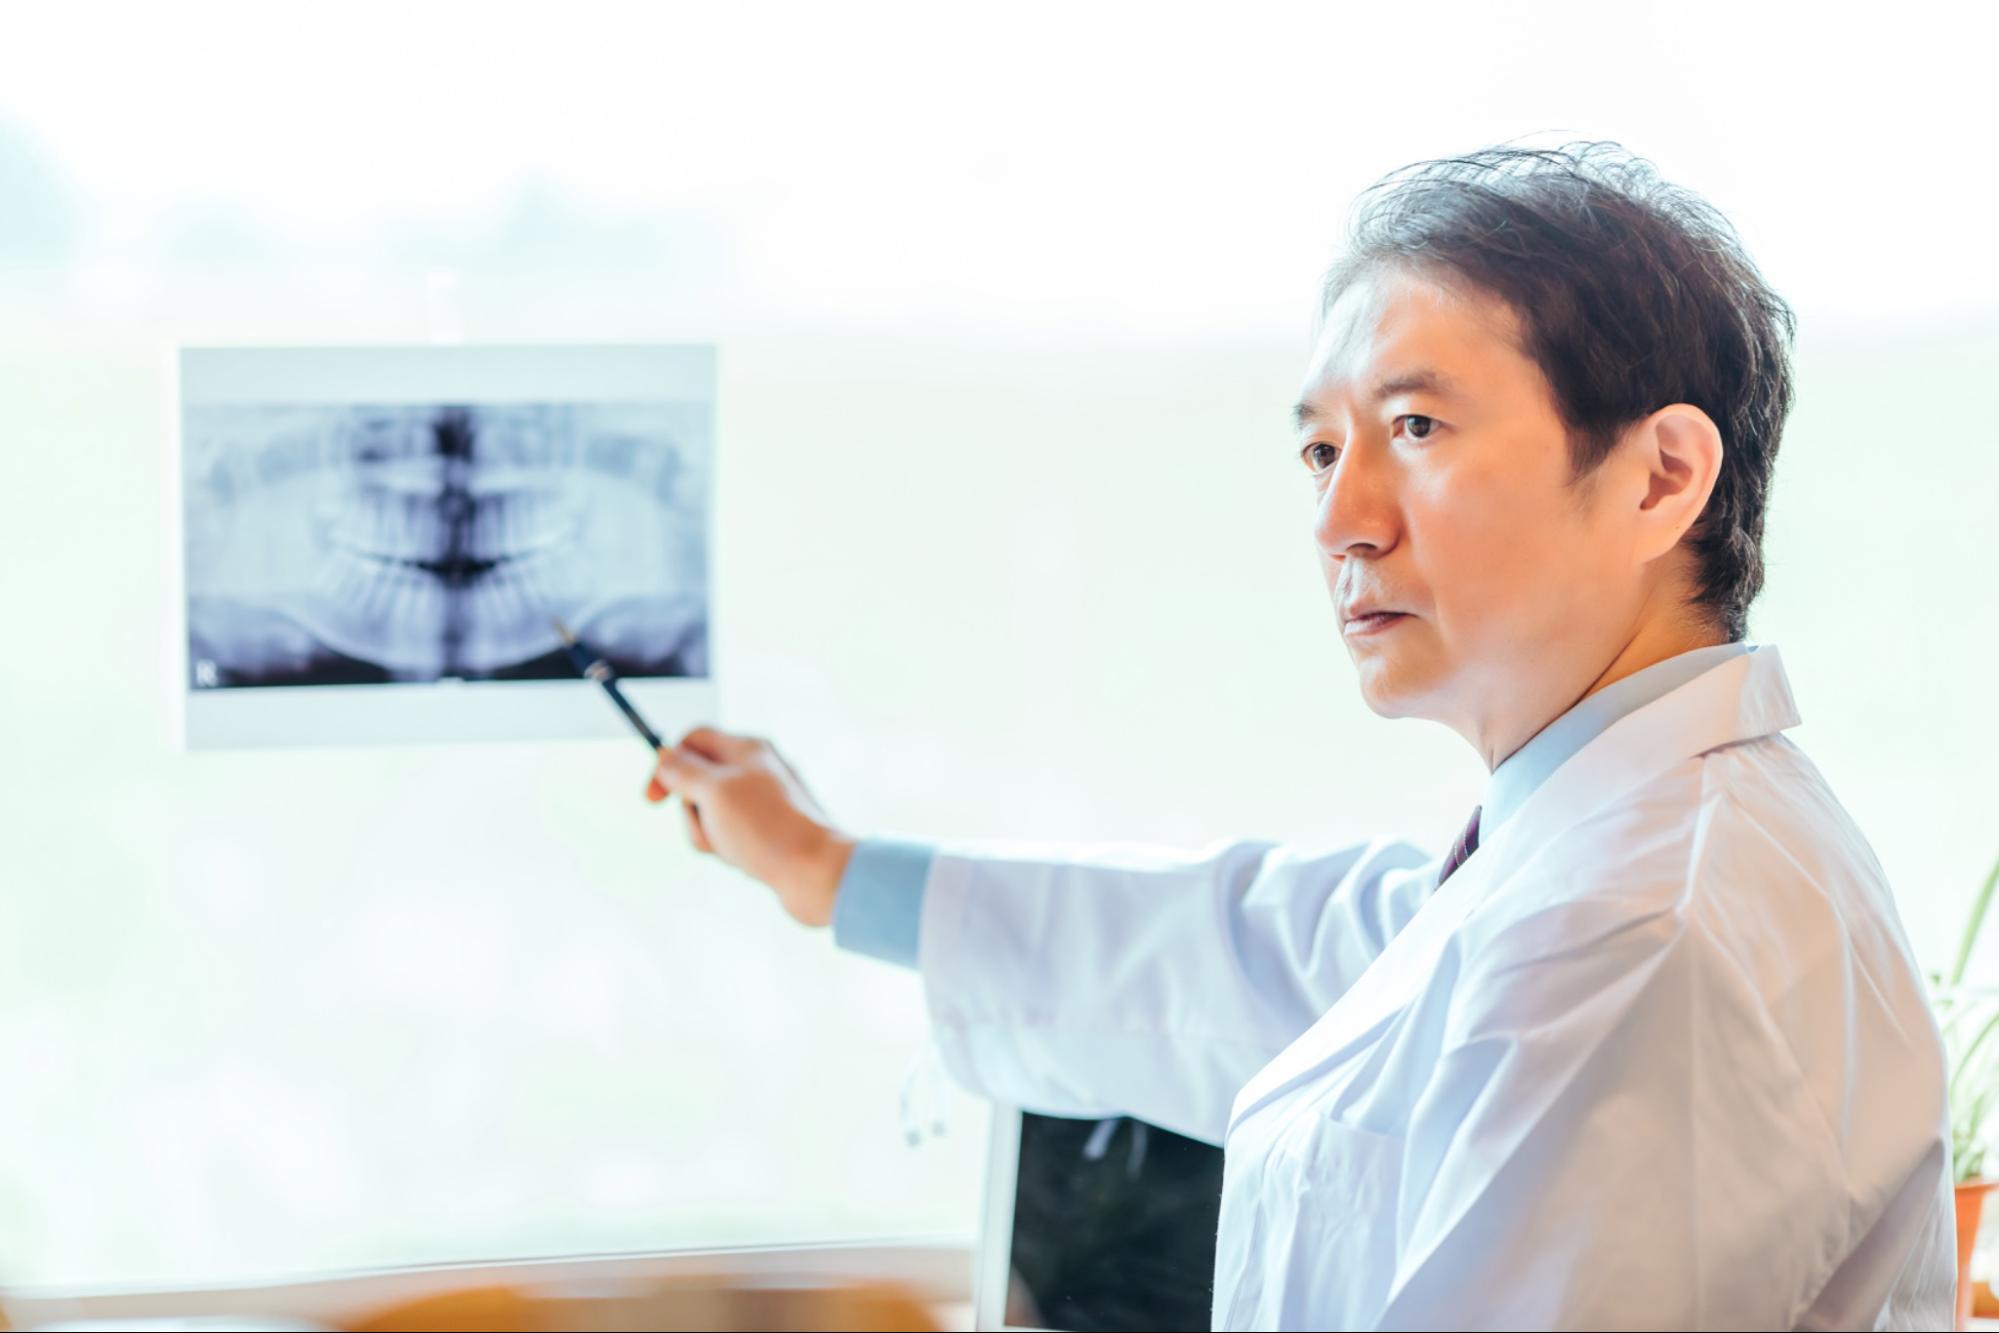

レントゲン検査

顎の骨の高さや密度、神経や血管の位置を把握するためにレントゲンを撮影します。特に下顎では、神経との距離を確認することが重要です。

2次元画像ではあるものの、インプラントの方向性を判断するのに役立ちます。

レントゲンは放射線量が少なく患者さんへの負担が少ないため、最初の診断ステップとして幅広く用いられています。

また過去に受けた口腔内の治療の確認にも役立ち、埋入位置を選ぶうえで大切な参考資料です。

基本的な構造把握には十分な情報が得られるため、歯科用CTと併用して使われることもあります。

歯科用CT検査

3次元的に顎の骨の構造を確認できるのが歯科用CT検査です。骨の厚みや密度、骨の内部構造まで立体的に把握できるため、より正確な診断が可能になります。

多くの医院で導入されている現在の標準的な検査です。

神経や血管の走行、上顎洞との距離なども正確に可視化できミスのない埋入計画を立てるうえで重要な役割です。

骨の質が十分でない場合どの位置なら埋入できるか、または補助処置が必要かの判断にもつながり高精度なデータで手術時間の短縮や侵襲の軽減にも貢献しています。